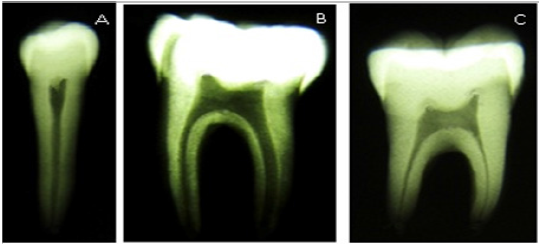

Es de hacer notar que aunque la muestra es algo reducida para intentar realizar clasificaciones morfogeométricas en dientes, en lo que a la población colonial se refiere, la misma es bastante significativa para nuestro estudio, ya que las investigaciones arqueológicas, en el área andina merideña, que han mantenido cierta continuidad en el tiempo, son relativamente nuevas y por lo tanto los vestigios antropológicos son escasos hasta el presente. Para observar la morfología interna de los dientes seleccionados se tomaron radiografías periapicales a cada uno de los dientes de ambas muestras. Para ello se emplearon películas radiográficas N0. 2 de velocidad E, marca kodak. Dichos dientes se posicionaron en la película con cera de utilidad para mantener su ubicación estable durante la exposición radiográfica. Al momento de la exposición radiográfica el rayo central se dirigió con una angulaciónperpendicular a la película con la finalidad que el objeto radiografiado se proyectara con dimensiones lo más cercanas posibles al tamaño real del diente.

Así mismo las radiografías fueron tomadas por un mismo operador con la finalidad de estandarizar la técnica y evitar errores humanos que posteriormente pudieran influir en la calidad de las imágenes.Para dicha toma radiográfica se utilizó un equipo de rayos X intraoral marca Gendex, modelo GX 770, empleando un tiempo de exposición de 28 décimas/seg. Una vez tomadas las radiografías fueron reveladas mediante el método visual por un mismo operador con la finalidad de lograr uniformidad en la densidad, el contraste y el detalle de las mismas (Imagen 1).

Posteriormente reveladas las películas, se procedió a su montaje en cartones para su adecuado almacenamiento y para la respectiva toma fotográfica de las mismas. Las imágenes se tomaron con una lupa Leica S6D con luz alógena incidente conectada a una cámara digital Canon PowerShot A590 IS a 2 aumentos. Todas las fotografías se tomaron bajo las mismas condiciones de luz y con la misma cámara. Posteriormente fueron digitalizadas con el Adobe PhotoShop CS3® (2007, Adobe Systems, Incorporate Systems Ltd.)Una vez obtenidas las fotografías y procesadas en un computador se procedió a la observación detallada de cada diente, específicamente de su silueta interna con la finalidad de llevar a cabo una segunda depuración de los grupos dentarios para dejar en la muestra solo aquellos dientes en donde desde el punto de vista radiográfico se observara nítidamente el contorno de la cámara pulpar y los conductos radiculares.